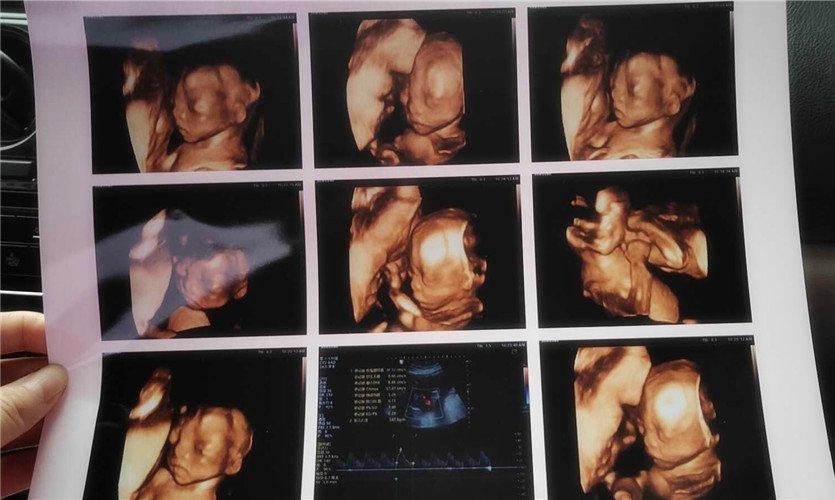

四維彩超是一種先進的醫(yī)學影像技術,通過實時觀察胎兒在母體內(nèi)的活動情況,為醫(yī)生提供了豐富的診斷信息,在四維彩超下,我們可以清晰地觀察到胎兒的蛋蛋(睪丸)的形態(tài)、位置和大小等特征,胎兒蛋蛋是男性生殖系統(tǒng)的重要組成部分,對于胎兒的生長發(fā)育具有重要意義。

在四維彩超下,胎兒蛋蛋呈現(xiàn)出特定的形態(tài)和外觀,通常情況下,胎兒蛋蛋呈現(xiàn)出圓形或橢圓形,表面光滑,內(nèi)部回聲均勻,隨著胎兒的發(fā)育,蛋蛋會逐漸增大,并呈現(xiàn)出明顯的性別特征,醫(yī)生可以通過四維彩超技術,對胎兒蛋蛋的大小、形態(tài)和位置進行評估,以判斷胎兒生殖系統(tǒng)的健康狀況。

胎兒蛋蛋的發(fā)育是一個復雜的過程,受到多種因素的影響,在胎兒發(fā)育的早期階段,蛋蛋位于腹腔內(nèi),隨著胎兒的生長發(fā)育,蛋蛋逐漸下降至陰囊,這個過程受到激素、遺傳和環(huán)境等多種因素的影響,在四維彩超的觀測下,我們可以實時了解胎兒蛋蛋的發(fā)育過程,及時發(fā)現(xiàn)異常情況并采取相應的治療措施。